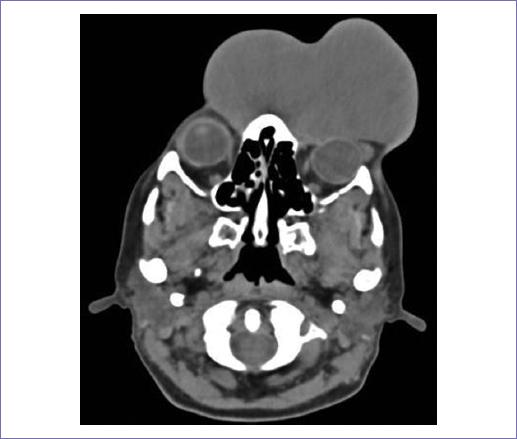

Al reporte de la tomografía axial computarizada (TC) de cuello, macizo facial y tórax se encontró una lesión exofítica localizada en región ciliar izquierda que abarca el dorso nasal y se extiende hacia la región frontal, desplaza el ojo en sentido posterior y lateral, que mide 10.8 x 11.7 x 5.2 cm (Fig. 2).

Figura 2 Tomografía axial computarizada de macizo facial. Se encontró una lesión exofítica localizada en región ciliar izquierda que abarca el dorso nasal y se extiende hacia la región frontal, desplaza el ojo en sentido posterior y lateral, que mide 10.8 x 11.7 x 5.2 cm.